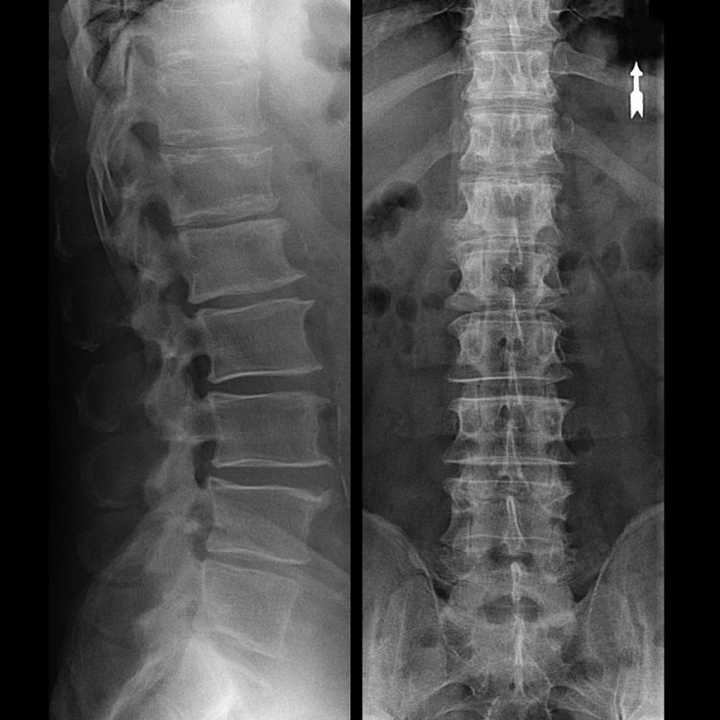

Servikal omurganın "röntgeni" ve hatta fleksiyon ve ekstansiyona yönelik fonksiyonel testlerde bile kıkırdak görülmez çünkü dokuları X ışınlarını iletir. Buna rağmen, omurların konumuna bağlı olarak, omurlararası disklerin yüksekliği, boynun fizyolojik eğriliğinin genel düzleşmesi - lordoz ve ayrıca kırılgan ve susuz kalmış omurlararası diskler nedeniyle yüzeylerinin uzun süreli tahrişi ile omurlarda marjinal büyümelerin varlığı hakkında genel sonuçlar çıkarılabilir. Fonksiyonel testler servikal omurgadaki instabilite tanısını doğrulayabilir.

Disklerin kendileri yalnızca BT veya MRI kullanılarak görülebildiğinden, kıkırdağın iç yapısını ve çıkıntılar ve fıtıklar gibi oluşumları netleştirmek için manyetik rezonans ve röntgen bilgisayarlı tomografi endikedir. Böylece, bu yöntemlerin yardımıyla tanı doğru bir şekilde konur ve tomografi sonucu, nöroşirürji bölümünde fıtığın cerrahi tedavisi için bir endikasyon, hatta güncel bir rehber olur.

- Fıtığın (varsa) ilerleyip ilerlemediğini anlamak için düzenli olarak en az iki projeksiyonlu lomber omurga röntgeni veya MRI çekebilirsiniz;